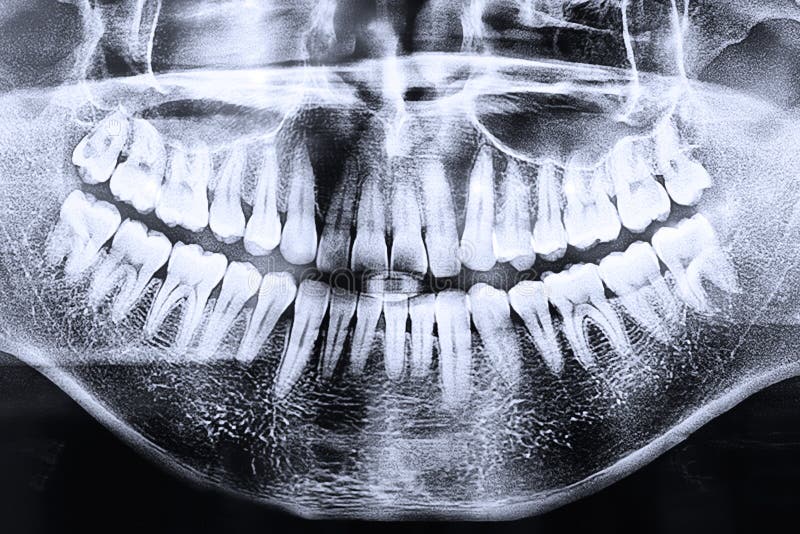

Фотографии и схемы для ОПТГ и мезиального прикуса